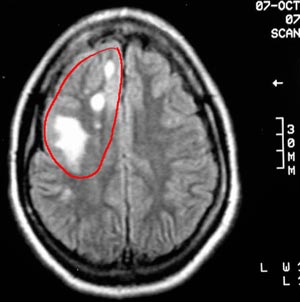

2b) Teratoma maduro

Figura 46 - Ressonância nuclear magnética antes da cirurgia